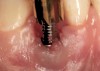

Fig 33. Excessive facial angulation of the implant placement shown with an abutment driver in the access screw hole.

Figure 33

Fig 34. A surgical cover screw was placed in an attempt to decoronate the implant and gain soft-tissue coverage in situ.

Figure 34

The crown and screw-retained custom abutment were removed, and a surgical cover screw was placed into the implant, thereby allowing spontaneous gingival augmentation in situ (Figure 33 and Figure 34). Note that the lingual aspect of the implant site was significantly more coronal than the labial aspect, which was positive because the defect would be limited to a facial–lingual defect. A fixed RBR bridge was cemented on the adjacent teeth and used as a tooth-supported transitional provisional restoration (Figure 35). A few weeks were allotted to let the soft tissue heal and migrate around the cover screw (Figure 36) to see if there would be complete coverage, thereby allowing a soft-tissue augmentation procedure to be performed with primary flap closure as in clinical scenario No. 2. The major obstacle in achieving a positive tissue response was that the implant depth was also deficient because the implant–abutment connection was at the level of the free gingival margin. It was decided that the best treatment option would be to remove the implant. A high-powered reverse-torque device (Fixture Remover Kit, NeoBiotech, www.neobiotechus.com) was used to remove the implant atraumatically (Figure 38 through Figure 41). The implant socket was allowed to heal for several months not unlike an extracted tooth (Figure 42). A new implant was placed in a better position from both a restorative and esthetic perspective (Figure 43), and after a few months of healing, a new crown was made (Figure 44). A satisfactory functional and esthetic result was achieved (Figure 45 and Figure 46) without employing pink porcelain.